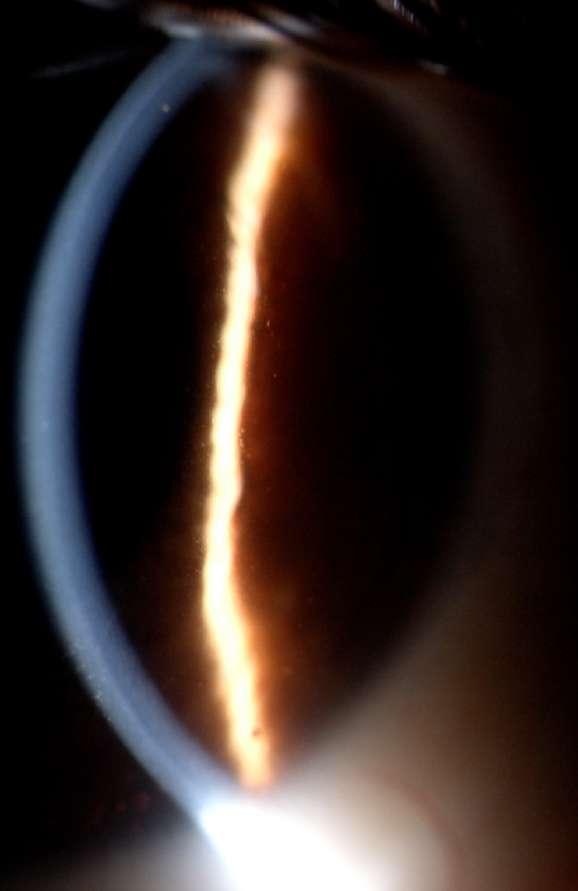

3.B. DISTROFIA ENDOTELIAL DE FUCHS (DCEF)

Caso aportado por Dr. Nathan Dukes

Cü Trastorno degenerativo específico y progresivo del endotelio corneal, donde la membrana de descemet (MD) puede estar muy afectada con engrosamiento y excrecencias posteriores denominadas clínicamente gutas.

ü Mujer de 60 años refiere que hace 6 meses presenta disminución de la agudeza visual que es más marcada al despertar. Al examen físico destacan guttas en la membrana de descemet del ojo derecho (Imagen A, B y C).

ü Al producirse discontinuidades en el endotelio fallan su función de barrera y actividad de sus bombas iónicas, lo que crea una insuficiencia en la resorción de fluidos y acumulación de agua en la córnea, con todo el cortejo sintomático consecuente.

ü La DCEF afecta al 4% de la población mayor de 40 años, y más a mujeres que a hombres. La mayoía de los casos es de transmisión autosómica dominante.

ü Estadío (E) clínico de la DCEF:

-E I: cambios sólo biomicroscópicos, con córnea guttata central, pigmentación endotelial variable y engrosamiento de la MD. Al progresar, toma aspecto de “metal batido”.

-E II: disminución visual indolora, más marcada al despertar, descrita como “neblina” (edema epitelial), desaparece a lo largo del día o puede quedarse como un fino velamiento grisaceo central. Microquistes epiteliales.

-E III: aparición de quistes y vesículas (bulas) epiteliales y subepiteliales, miccroscópicas y macroscópicas. Edema estromal central o paracentral, en forma de vidreo esmerilado. Estrías y pliegues en la MD.

-E IV: cicatrización subepitelial con marcada disminución de la visión y dolor, menor edema, puede desarrollar neovascularización superficial. Vesículas “enquistadas”. Fibrosis subepitelial hipertrófica con apariencia de queloides. A B